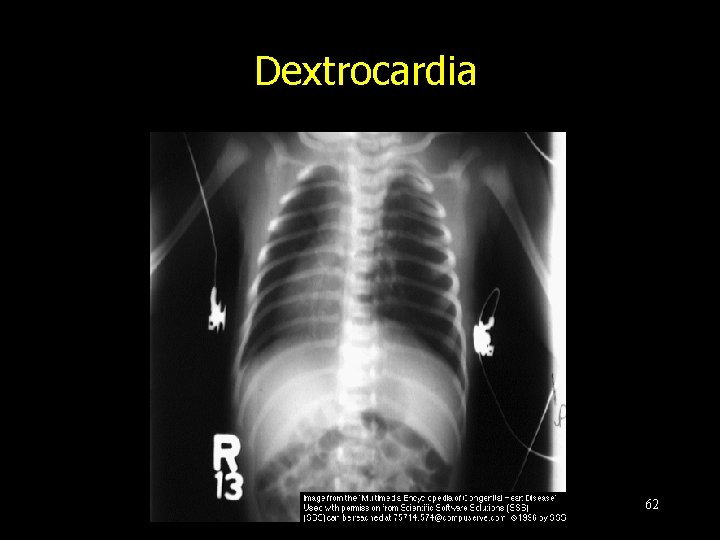

Cardiac malpositions and heterotaxy 61

Dextrocardia 62

- Slides: 62